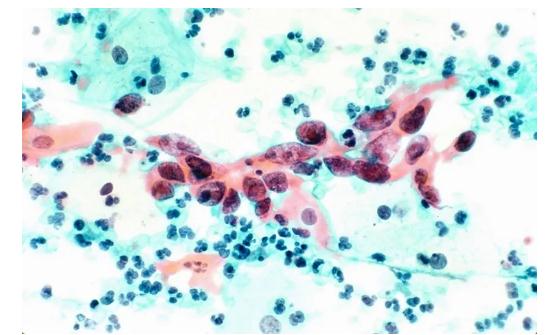

光学显微镜下的宫颈癌细胞。/ quanjing